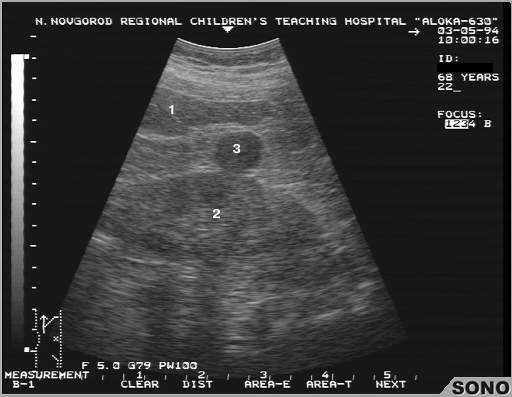

Взрослый тип поликистоза почки